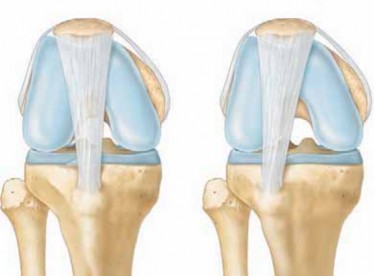

Revision Total Knee Arthroplasty With Extensor Mechanism Repair DEFINITION Patellar tendon rupture following …